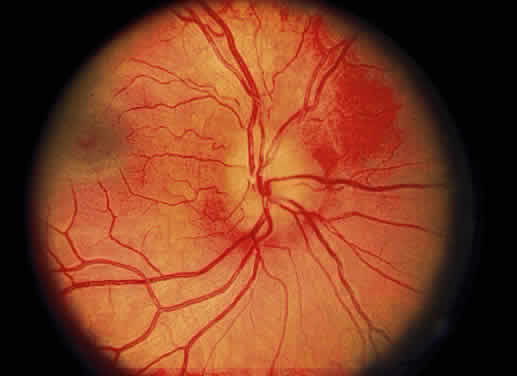

Cotton-wool spots are observed mainly in the posterior pole of the retina (Fig.23) The reason for this geographic restriction is not clear. Occlusion of

the most superficial radially oriented peripapillary capillaries (confined

in distribution to the posterior pole) has been implicated in the

pathogenesis of cotton-wool spots.9 It is also possible that nerve fiber infarcts in the periphery are not

visualized because there is insufficient inspissated axoplasmic material

in this location.  Fig. 23. Multiple cotton-wool spots along with retinal hemorrhages in a superior

temporal branch retinal vein occlusion. Fig. 23. Multiple cotton-wool spots along with retinal hemorrhages in a superior

temporal branch retinal vein occlusion.